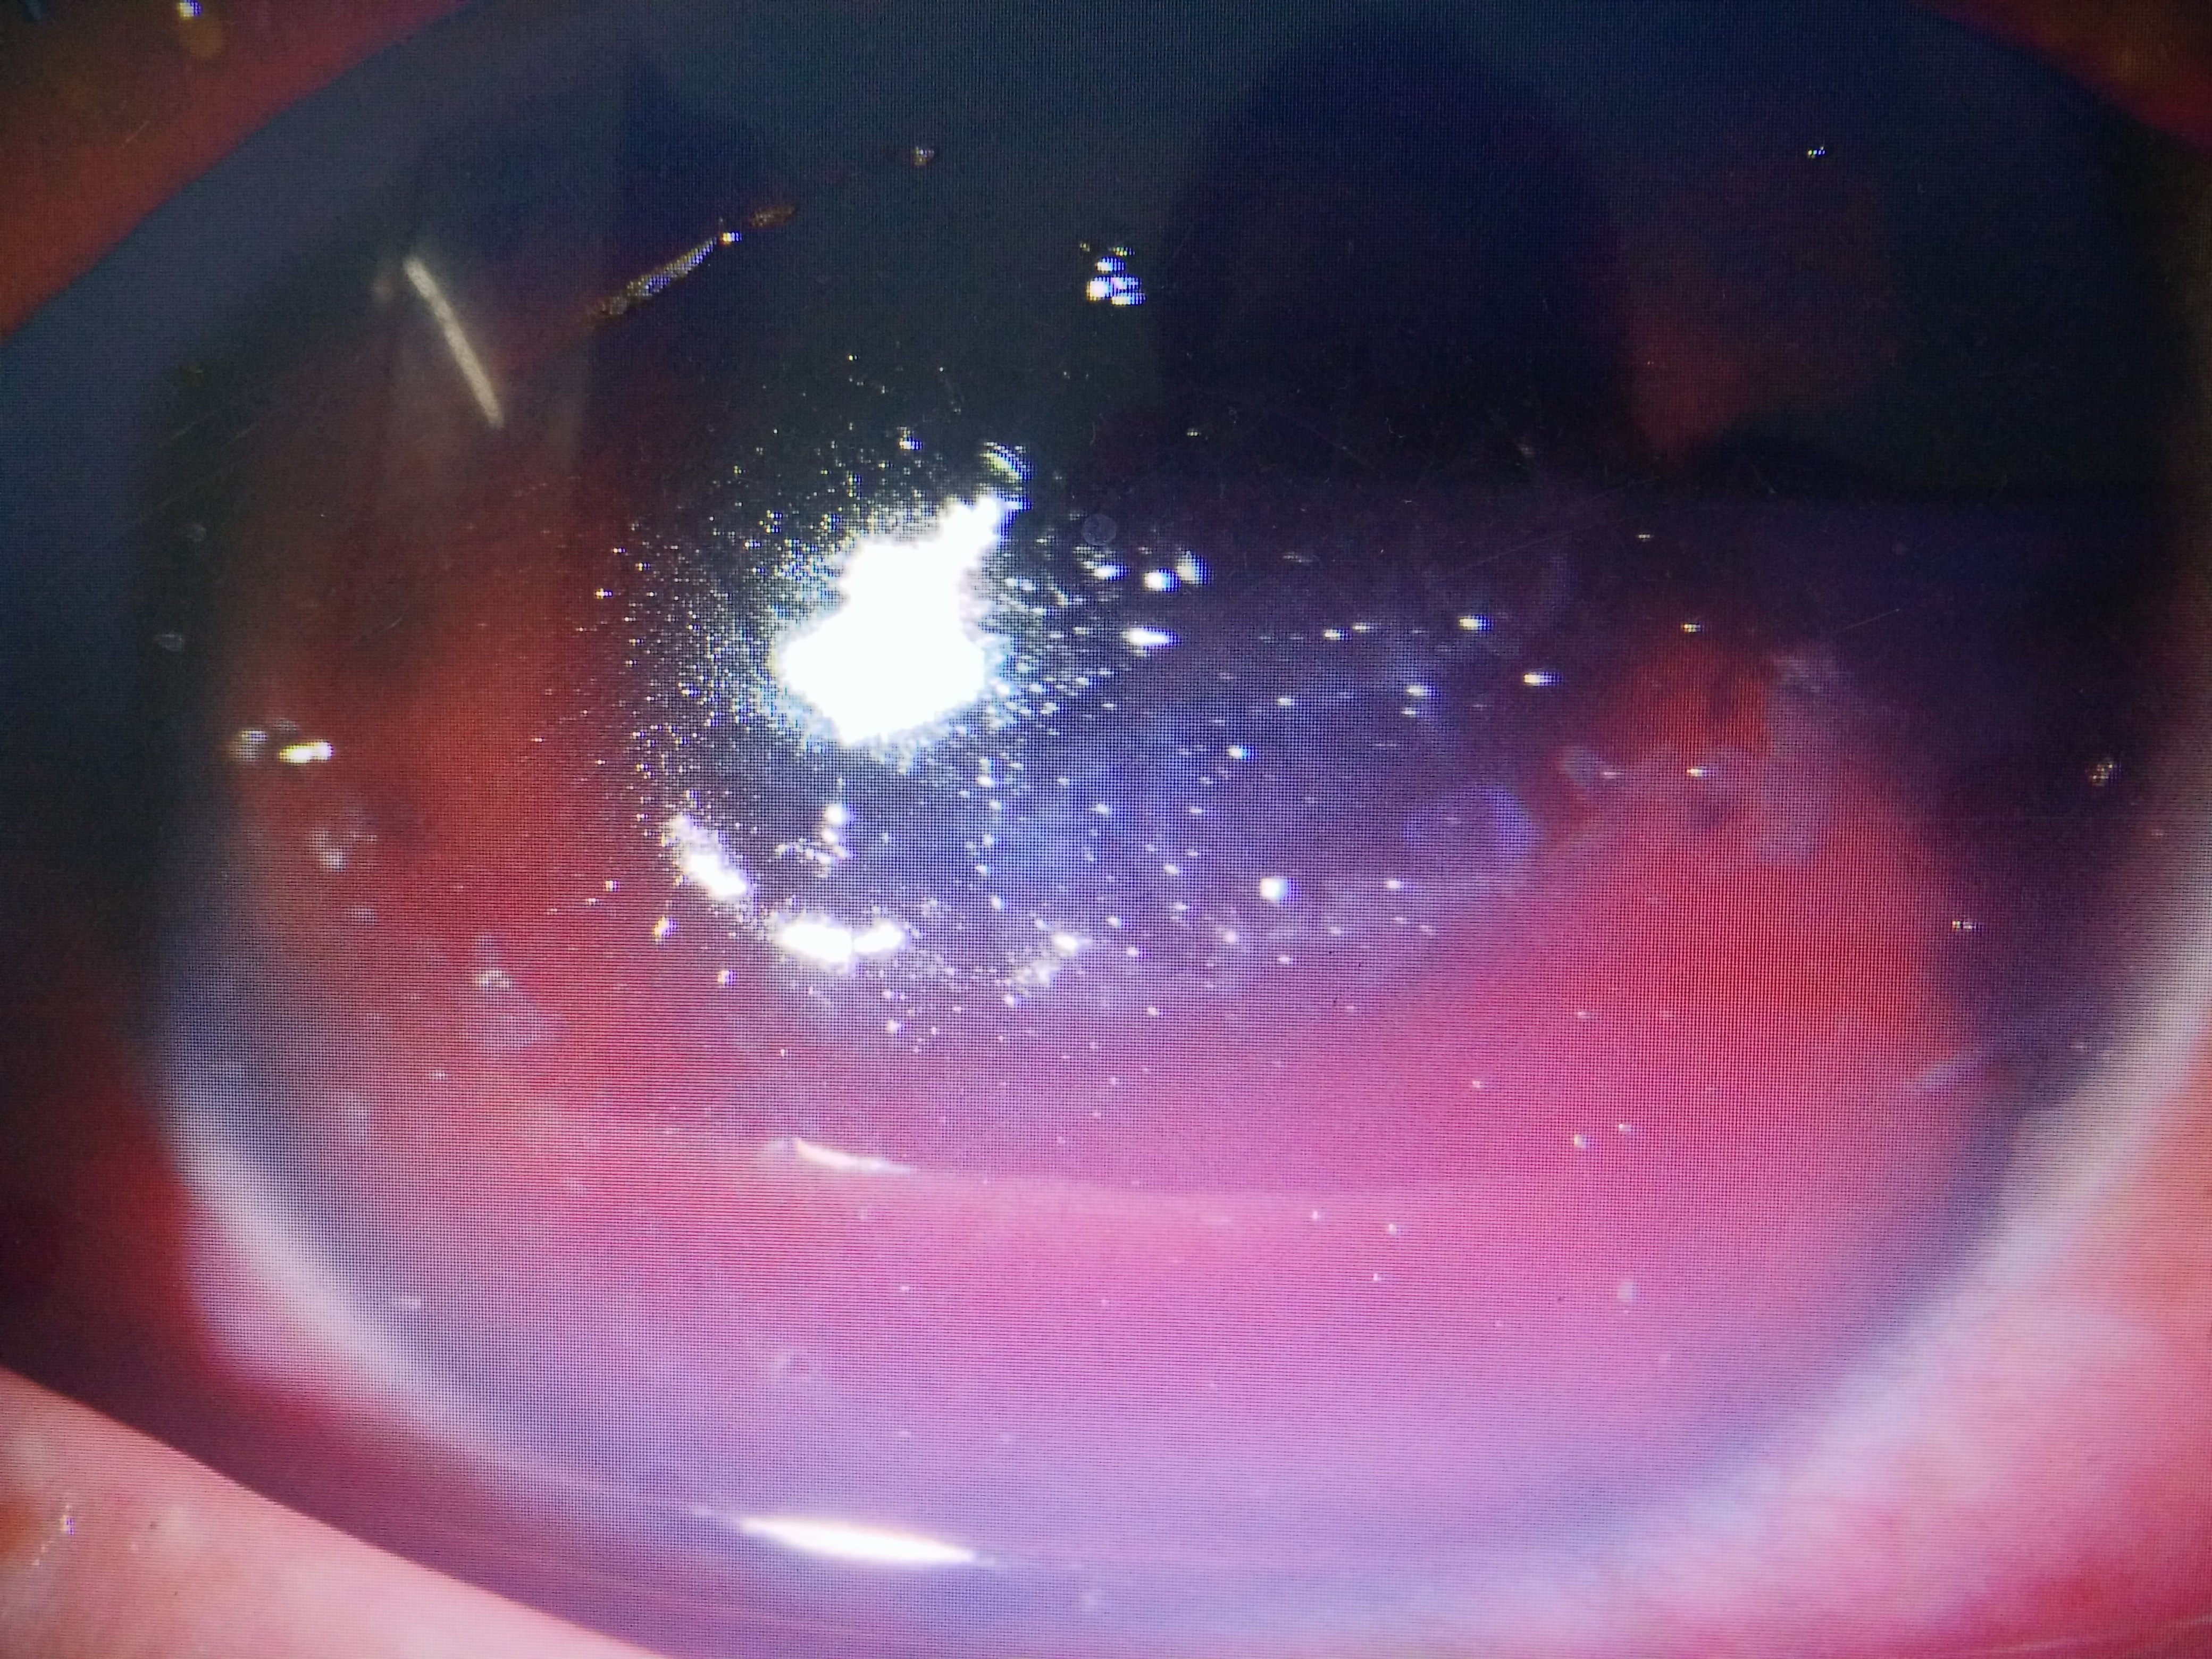

大量异物高度撞击角膜组织,可导致深浅不同的角膜层间异物,严重者可